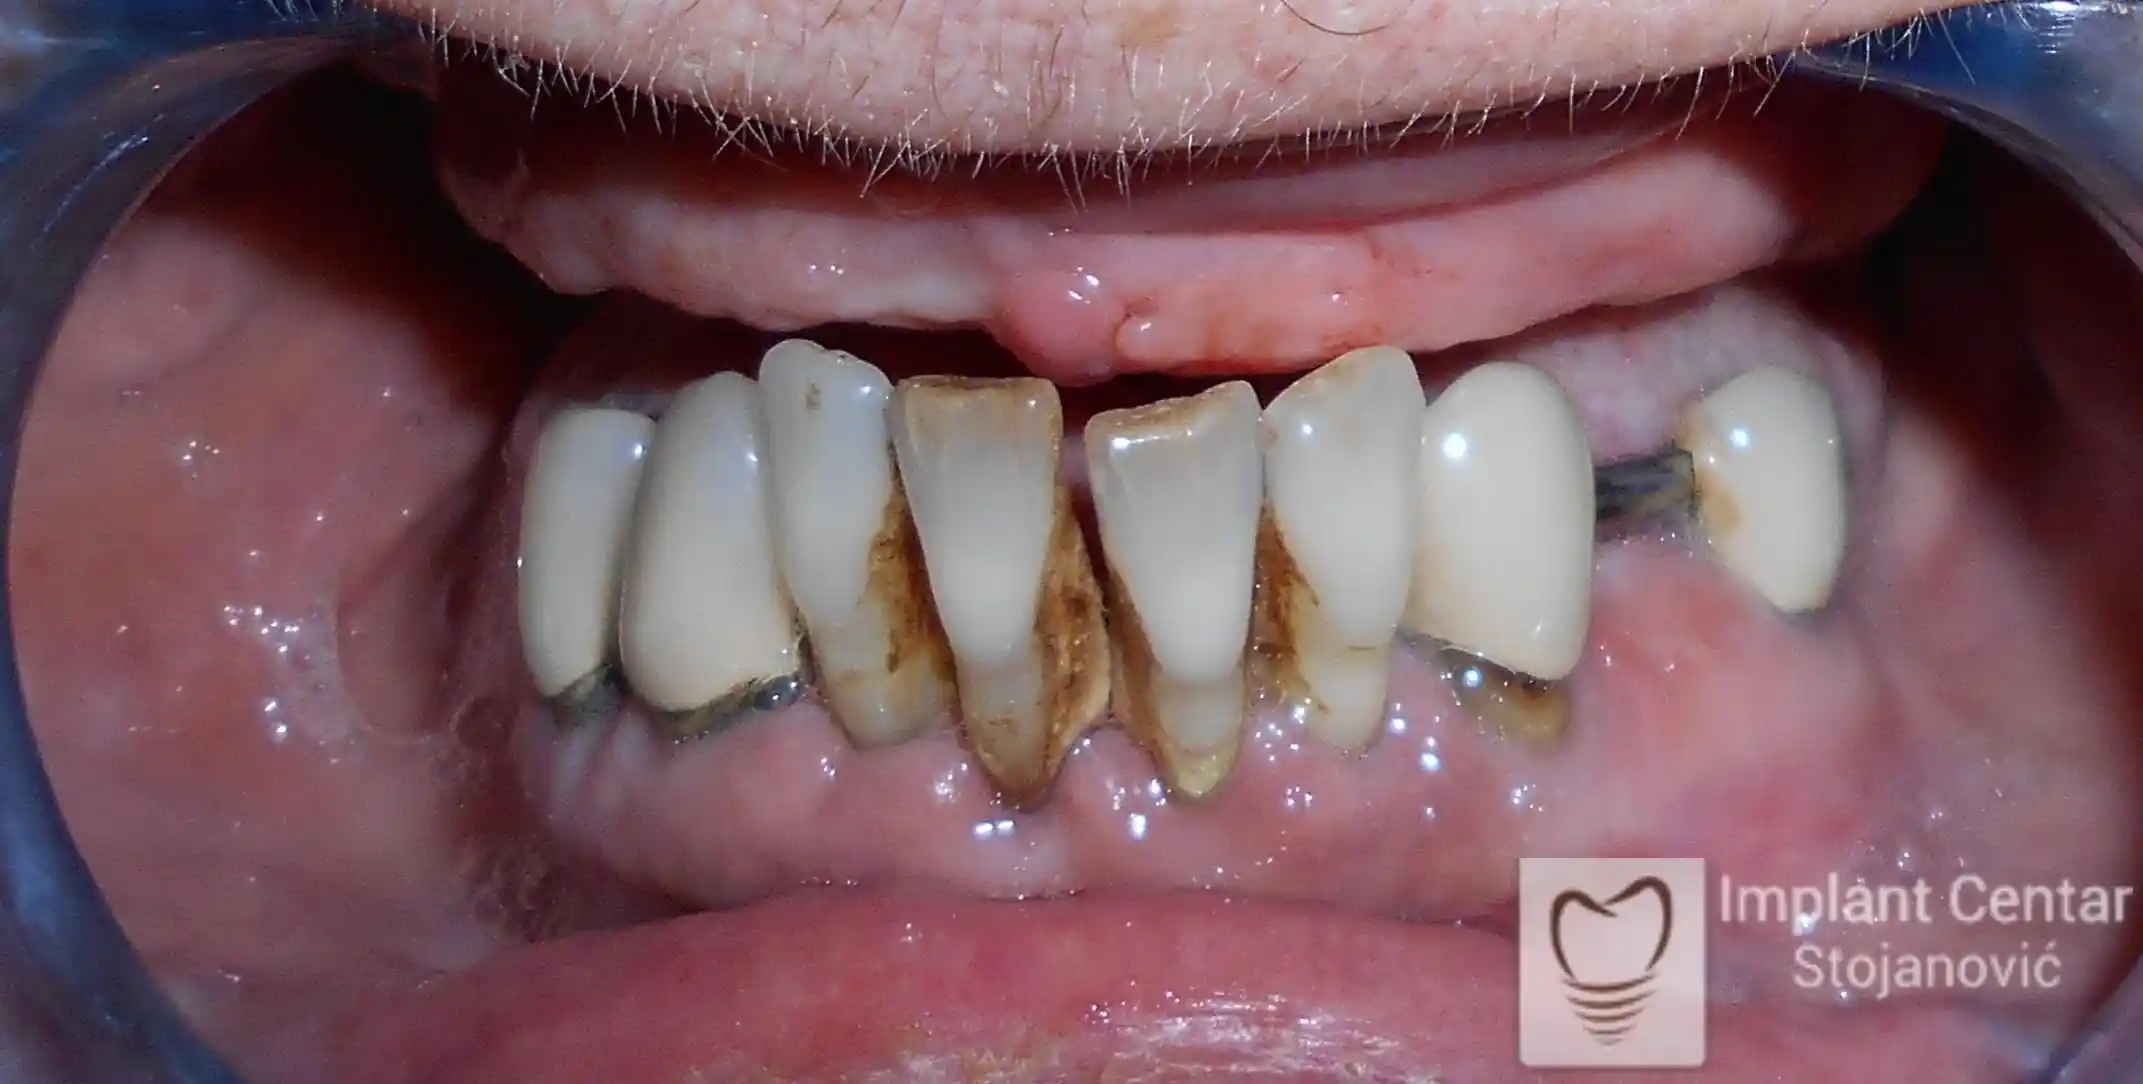

Na slikama 1 i 2 prikazan je klinički izgled pacijenta pre početka terapije. Nakon detaljnog kliničkog pregleda, analize radioloških snimaka, kao i razgovora sa pacijentom o njegovim željama i očekivanjima, izrađen je sveobuhvatan plan terapije. Terapija je podrazumevala vađenje preostalih zuba, ugradnju dentalnih implantata i izradu fiksnog protetskog rada na implantatima.

Tokom perioda osteointegracije, pacijent je bio zbrinut fiksnim privremenim krunicama na implantatima, čime su očuvani estetika i funkcija. Nakon završetka perioda integracije, izrađeni su definitivni cirkonijum-keramički mostovi (slika 6 i 7 ).

Pacijent je izuzetno zadovoljan postignutim rezultatom, jer su u potpunosti vraćeni prirodan izgled osmeha i puna oralna funkcija.